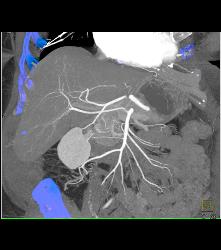

Right Hepatic Artery Arises Off the Superior Mesenteric Artery (SMA) and Left Hepatic Artery Arises Off the Aorta